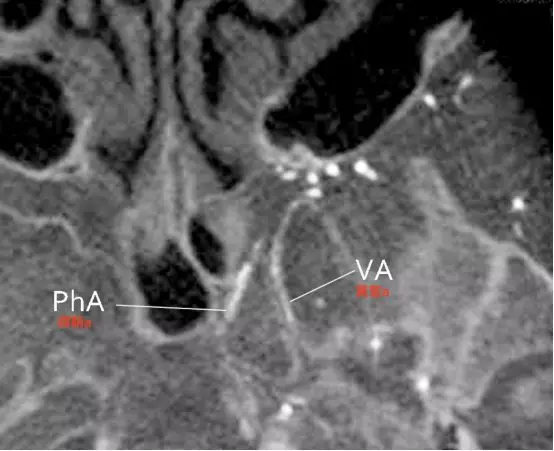

Tanoue等报道了一例颈内动脉近端闭塞,左侧颈外动脉CTA水平位重建,可观察到翼管动脉、圆孔动脉和腭鞘动脉等(Tanoue 2013)。

a,显示翼管动脉向后走行进入翼管(Tanoue 2013)。

b,腭鞘动脉,又称咽动脉(pharyngeal artery)发出紧邻翼管动脉,向后下方走行,与翼腭神经伴行,通过腭鞘管(咽管)(Tanoue 2013)。

圆孔动脉向后上走行,与上颌神经伴行,进入圆孔(Tanoue 2013)。圆孔位于翼管上方。